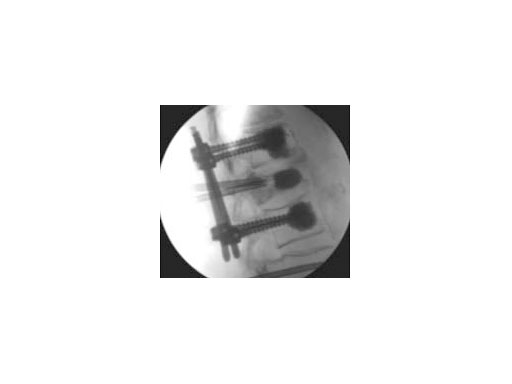

Both guide wire and trocar can be inserted through either a transpedicular (Fig 2a) or extrapedicular (Fig 2b) approach. The trocar allows access in a single step while the wire guide is first used to create a path for the access instruments.